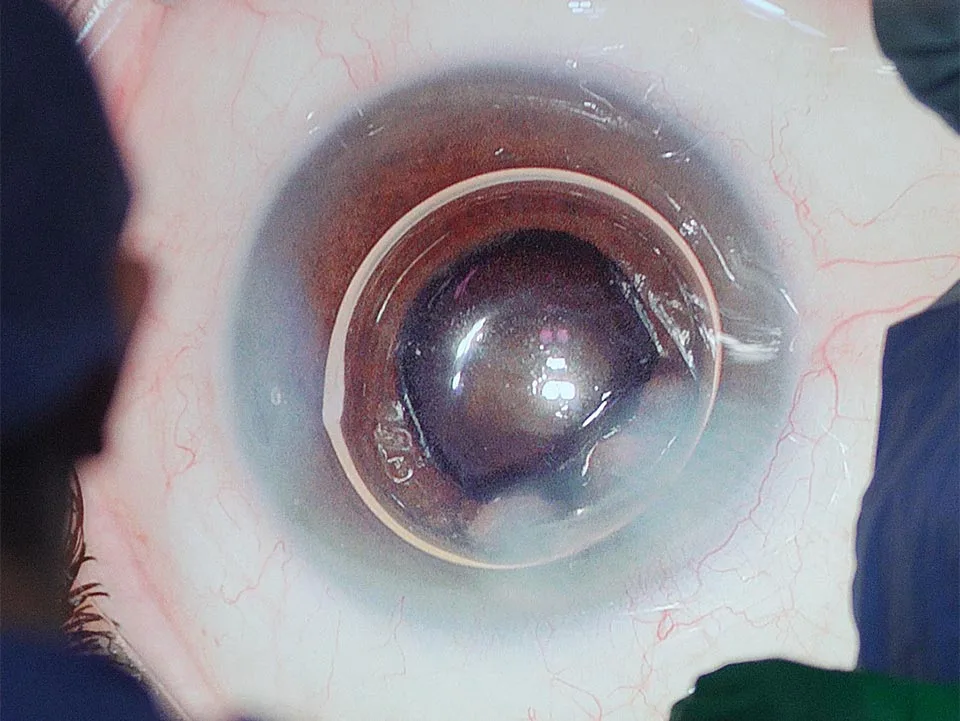

Segmento Anterior

- Cataratas

- Cirugía del Cristalino

- Queratocono

- Trasplantes de Córnea